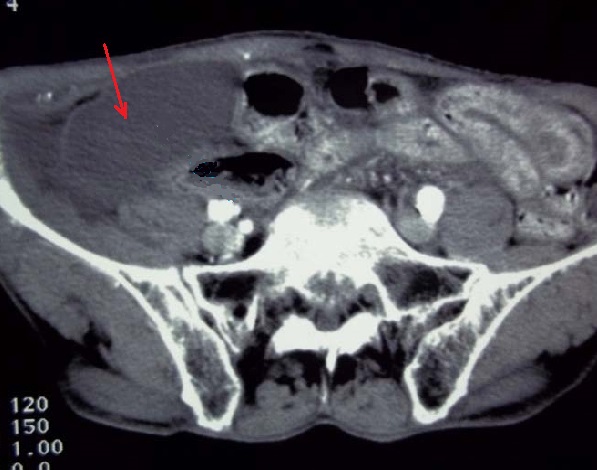

Volvulus biliaire avec image

de vesicule biliaire tres distendue eloingnee

au bas de l'abdomen . Image de moindre de

rehaussemant et image de epanchement

perivesiculaire est encore se presenter ( fleche

rouge ) : Image TDM + contrast en coupe axiale

tres bas a travers deux cretes iliacques |